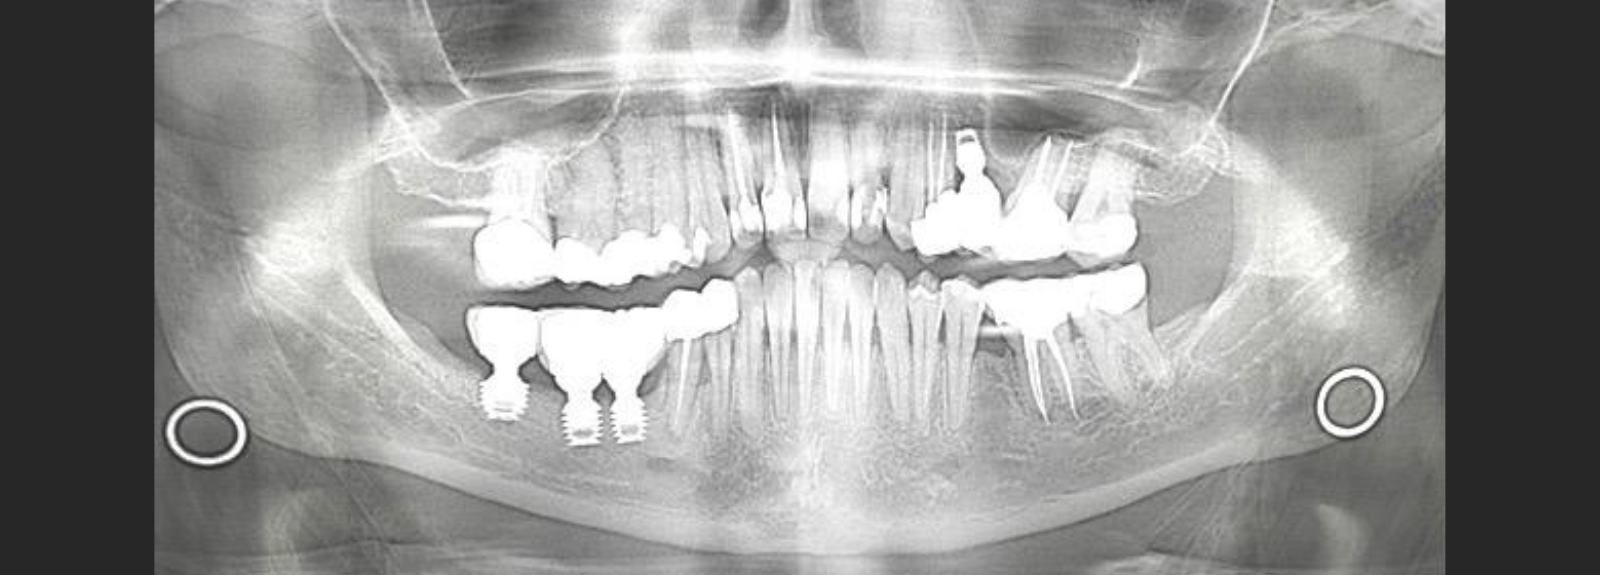

What is a CBCT Scan? Cone Beam Computed Tomography (CBCT) is anadvanced dental and maxillofacial imaging modalitythat produces high-resolution three-dimensional (3D)images of the teeth, jaws, nerve pathways, andcraniofacial structures. Unlike conventional two-dimensional imaging such aspanoramic or intraoral radiographs, CBCT…